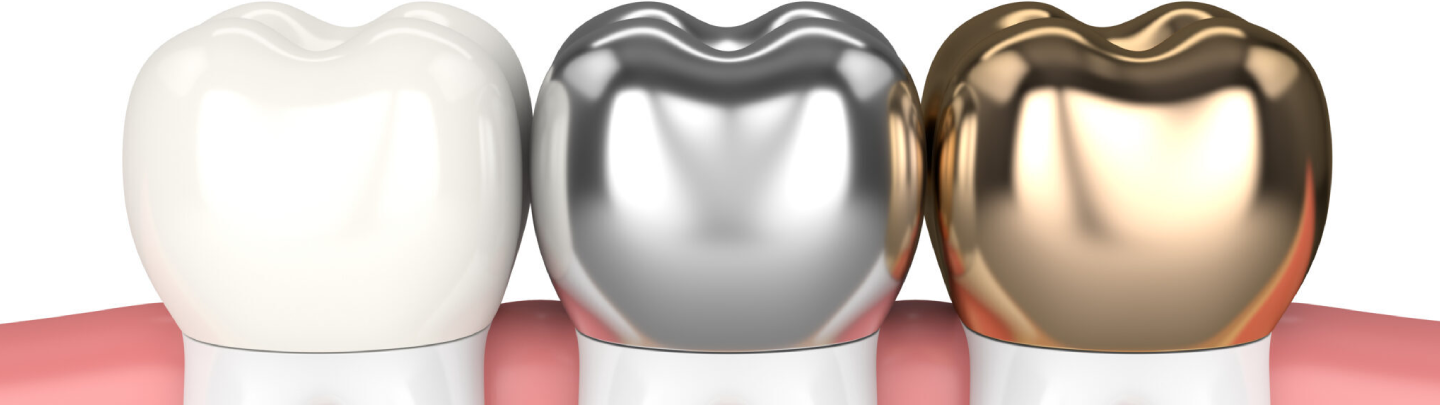

Crowns can be made from a variety of materials, depending on the requirements. The most common types of crown materials are metals, tooth-colored porcelain, or a combination of the two. We’ll help you to select the right crown material based on your aesthetic goals. We offer porcelain, zirconia and E-MAX crowns to suit your requirements.

Types of Dental Crowns

- Porcelain Crowns – Natural-looking and ideal for front teeth.

- Ceramic Crowns – Aesthetic and durable for both front and back teeth.

- Metal Crowns – Extremely strong and used for molars under heavy chewing pressure.

- Porcelain-Fused-to-Metal (PFM) Crowns – Combines strength with a natural appearance.

- Same-Day Crowns – Crafted using advanced CEREC technology for immediate restoration.